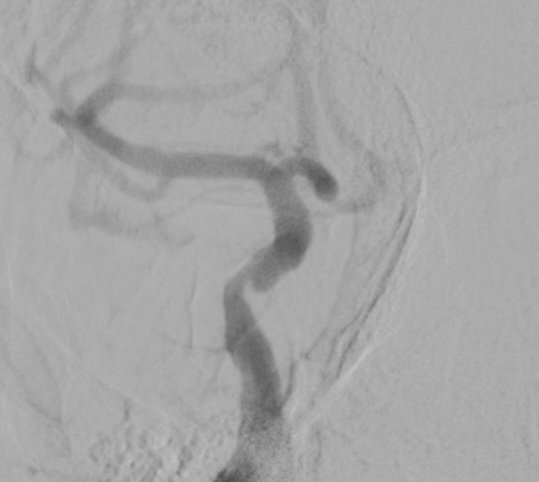

همه در یک بیمار. کاروتید راست:دایسکشن کاروتید چپ: تنگی شدید ورتبرال چپ: بسته شدن کامل از ابتدای شریان ورتبرال راست: دایسکشن و آنوریسم. درمان: استنت کویل در ورتبرال راست و نیز استنت کاروتید چپ. ادامه درمان با ضد پلاکت.